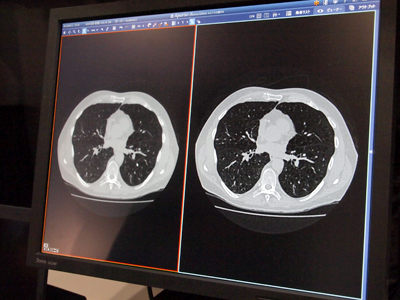

テラリコン社「Aquarius iNtuition Server」は,CTコロノグラフィ(CTC)の保険適用を受けて,ソフトウエアの強化を行っている。「Fly-Through」は,大腸の抽出,中心線の作成を自動処理し,スパイン,プローン,ラテラルの3相のflat viewを同時に観察することができる。また,開発中のCTC用CAD機能も紹介された。Aquarius iNtuition Serverを取得後,サーバ上で病変を判別して青色のポイントでマーキングする。アキシャル像,MPR像,VR像でマーキング表示することで,病変の把握を容易にしている。このCAD機能については,肺がん用のソフトウエアも開発を進めている。

このほか,CTの画像再構成法として注目される逐次近似法のソフトウエアの開発も行っている。これは低線量CTのデータをAquarius iNtuition Serverでノイズ除去フィルタ処理を行うもの。サーバ上で集中的に処理できるので,装置ごとに処理を行うことなく,効率的に高画質化を図れる。

![]() 「Aquarius iNtuition Server」の「Fly-Through」 |

![]() 開発中の「Aquarius iNtuition Server」のCAD機能 |

![]() 「Aquarius iNtuition Server」の逐次近似再構成ソフトウエア |